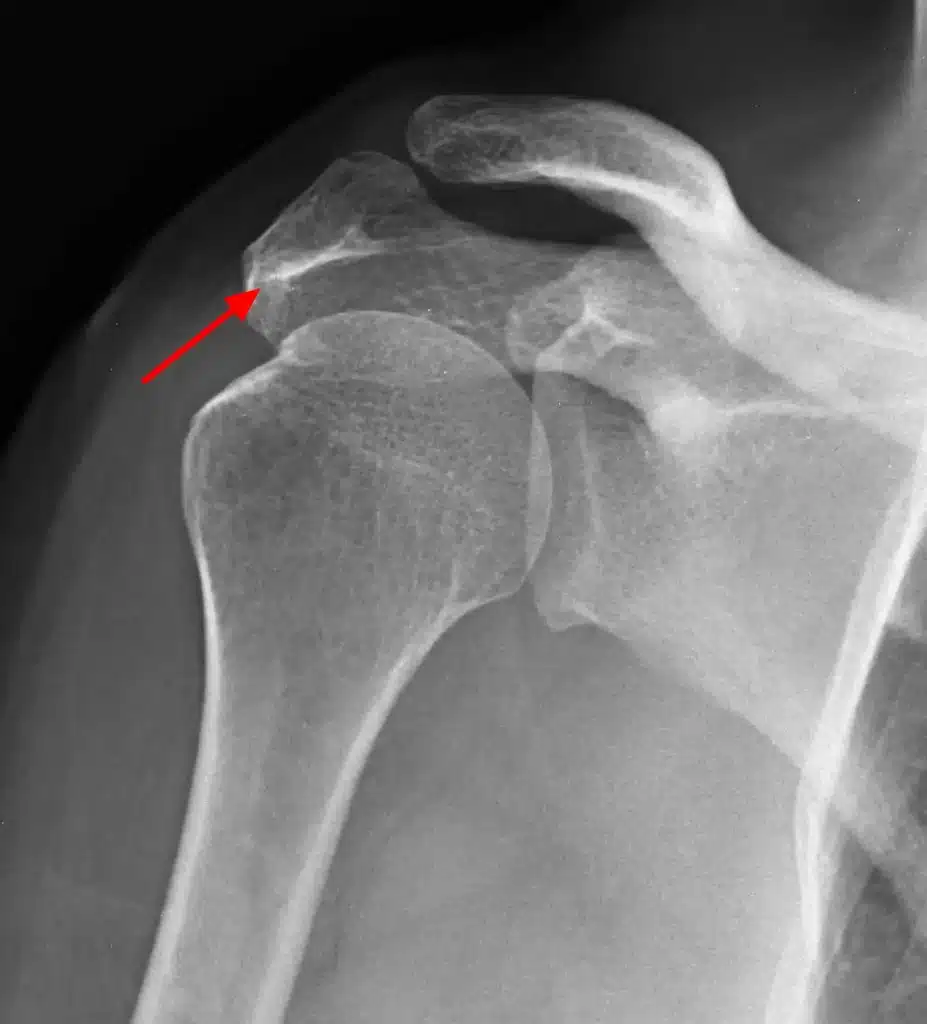

استئوفیت و خار استخوانی چیست

استئوفیت و خار استخوانی: تعریف، علل و عوامل خطر عنوان توضیحات تعریف استئوفیت (خار استخوانی) زائدههای استخوانی کوچک و صاف که در لبههای استخوانها، معمولاً در نزدیکی مفاصل، رشد میکنند. علل ایجاد استئوفیت آرتروز (شایعترین علت)، آسیبهای مفصلی، ساییدگی و پارگی مفاصل، التهاب مزمن تاندونها و رباطها، اسپوندیلوز (آرتروز گردن و کمر) عوامل خطر افزایش […]